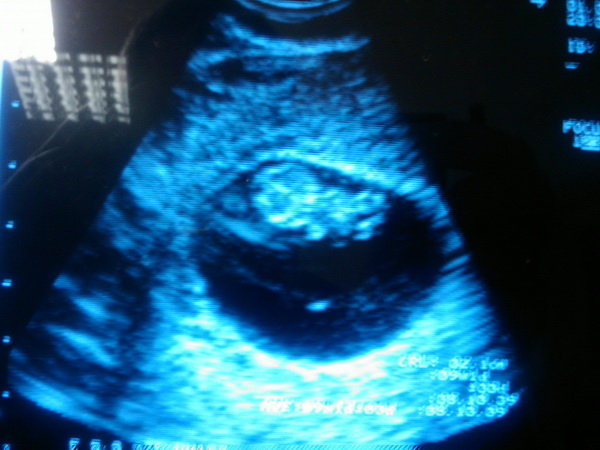

én is kíváncsi vagyok, bár eddig minden lehetséges tudományos és ezoterikus eszköz lányt mutat, na meg Lili is azt mondja. Jónás, kínai fogamzásnaptár, inga, apu feleségének a kütyüje, na és ugye inszemkor még nem volt megrepedve a tüsző, lehet, hogy csak másnap repedt, ez is a lányra utal. Bár Pötty kicsit nagyobb, mint Lili volt ilyenkor, de tulajdonképpen mindegy is. Örülünk, hogy van, és kész